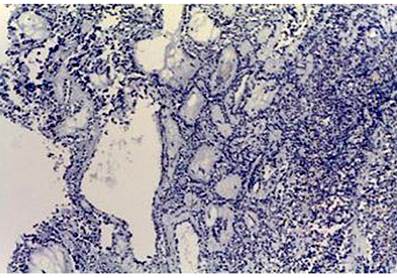

Histológicamente, todos los casos presentaron un patrón sólido y pseudopapilar, con células de apariencia epitelioide; un caso presentó células de aspecto sarcomatoide y otros dos con presencia de células gigantes multinucleadas. El pleomorfismo nuclear estuvo ausente o fue leve en la mayoría, solo hubo un caso con pleomorfismo grave y presencia de mitosis atípicas, el cual corresponde a una paciente femenina de 56 años. En el resto de tumores, la actividad mitótica fue escasa o nula sin figuras atípicas (Figuras 1,2, 3,4,5,6,7,8 y9).

El tumor sólido pseudopapilar afecta principalmente a mujeres jóvenes, con una relación 9:1, se presenta con síntomas abdominales inespecíficos, como abdomen agudo en caso de ruptura de la lesión por trauma o como hallazgo incidental en las imágenes radiológicas1,4. En La tomografía axial computarizada (TAC) y resonancia magnética (RM) de abdomen se observa una masa bien encapsulada con densidades o intensidades heterogéneas, lo que refleja degeneración quística y hemorragia dentro del tumor5. Macroscópicamente, alcanzan medidas de 10 cm o más; son masas bien circunscritas, sólidas y quísticas; las áreas sólidas tienen una consistencia friable y las áreas quísticas presentan necrosis y hemorragia5-7. Microscópicamente, tienen una arquitectura sólida y pseudopapilar alrededor de los vasos sanguíneos delgados8. Las células neoplásicas son discohesivas, de aspecto epitelioide con núcleos redondos y hendiduras, no hay atipia nuclear importante y las mitosis son infrecuentes. Las células tienden a alejarse de los vasos sanguíneos y se degeneran, lo que produce las extensas áreas de necrosis; las células que se mantienen alrededor de los tallos fibrovasculares forman una o múltiples capas que dan el aspecto pseudopapilar característico de la lesión. El estroma puede tener grados variables de hialinización. Pueden existir pequeños grupos de histiocitos epitelioides que acompañan la lesión1,4-8.